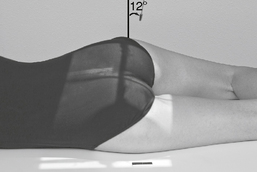

Location of the femoral head and neck regions can be accurately determined by first drawing an imaginary line between two landmarks, the ASIS and the symphysis pubis. The midpoint of this line is determined, from which a perpendicular imaginary line is drawn to locate the head and/or neck. The femoral head (A) is approximately 1.5″ (4 cm) down on this line. The midfemoral neck (B) is approximately 2.5″ (6-7 cm) down, as shown in the photo below.